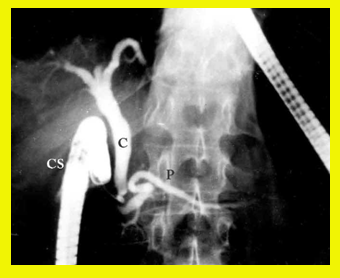

| תצלום 8.8: Percutanous trans-hepatic cholangiography (PTC) - תמונה שמאלית החץ מצביע על המחט והצנתר המוחדרים לדרכי המרה תמונה ימנית חץ מצביע על פגם בדרכי המרה G-כיס מרה 1- צינור מרה משותף. | |

- Percutaneus trans-hepatic cholangiography (PTC) (תצלום 8.8). בשיטה זו אפשר להדגים את דרכי המרה על-ידי ניקור מלעורי של הכבד. בניקור חודרים לכלי מרה בכבד ודרכו מזריקים חומר ניגוד לדרכי המרה ה"צובע" את העץ הביליארי. שיטה זו טובה בלוקים בערכי בילירובין גבוהים, שכן בהם אין לבצע את בדיקות הניגוד.

- בשיטה זו ניתן לבצע גם ניקוז קבוע של דרכי המרה על-ידי החדרת נקז לתוך דרכי המרה (PTD - percutaneus trans-hepatic drainage). התנאי להצלחת הבדיקה הוא דרכי מרה מורחבות, שאפשר לזהות בבדיקת אולטרה-סאונד של דרכי המרה (תמונה 9.8).

- בגישה זו אפשר גם לנקז את כיס המרה בחולים עם חסימות בצינור כיס המרה (איור 4.8) או לשלוף אבנים בעזרת מכשיר מיוחד ללכידת אבנים (Basket) (תצלום 10.8).